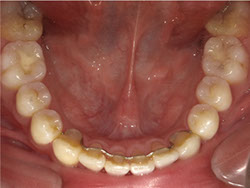

1期治療でスケルトンタイプの拡大装置で歯列拡大後、上下第一小臼歯を抜歯して口元もキレイになりました。

矯正前

矯正中

矯正終了後